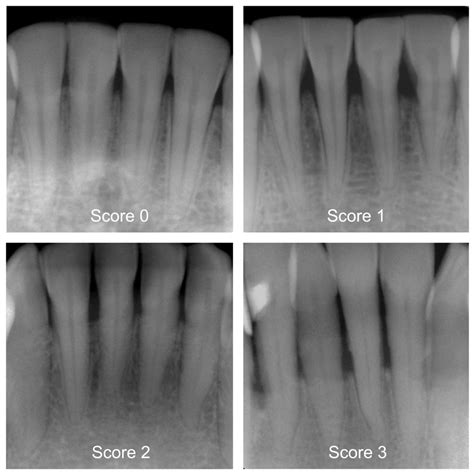

Diagnostic Tool Purpose

Dental X-rays Detects changes in bone density and identifies hidden areas of infection.

Periodontal Probing Measures the depth of pockets between the tooth and the gum to assess inflammation and loss.